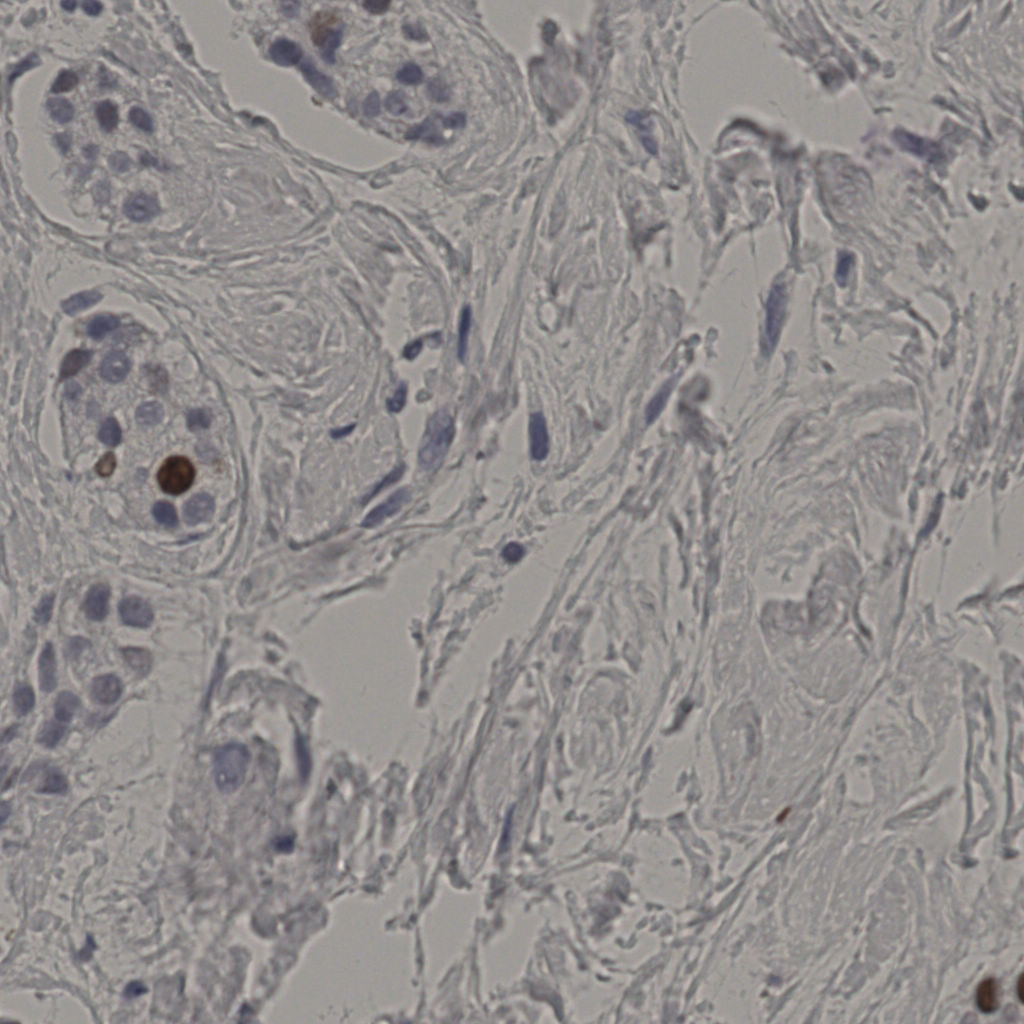

标记后

标记前

5.31%

Ki67 指数

阴 19502

阳 1093